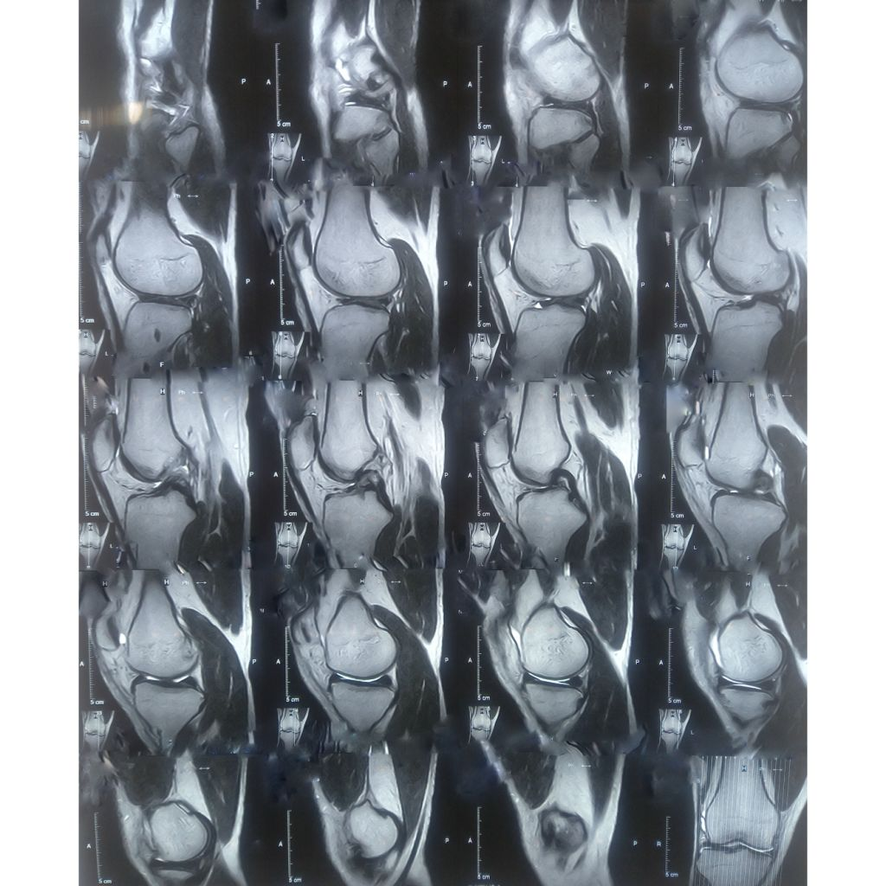

슬개골 탈구의 이해와 위험요인

고양이의 슬개골 탈구는 흔히 발생하는 문제로, 보호자의 꼼꼼한 관리가 필요합니다. 본 섹션에서는 슬개골 탈구의 정의, 주요 위험 요인, 그리고 예방의 중요성에 대해 자세히 살펴보겠습니다.

슬개골 탈구는 고양이의 뒷다리에 위치한 무릎뼈인 슬개골이 정상적인 위치에서 벗어나는 상태를 의미합니다. 슬개골 탈구가 발생하면 고양이가 걷는 데 어려움을 겪고, 장기적으로는 관절염 등의 합병증으로 이어질 수 있습니다. 이 문제는 특히 소형 고양이나 특정 품종에서 빈번히 발생하므로, 예방과 관리가 필수적입니다.

슬개골 탈구는 초기에는 눈에 잘 띄지 않는 증상으로 시작할 수 있습니다. 따라서 정기적인 건강검진은 매우 중요합니다. 전문 수의사는 고양이의 관절 건강을 평가하여 조기 발견 및 치료를 가능하게 합니다. 특히 슬개골 탈구의 위험이 높은 품종의 경우, 이 검사 주기가 더욱 필수적입니다.